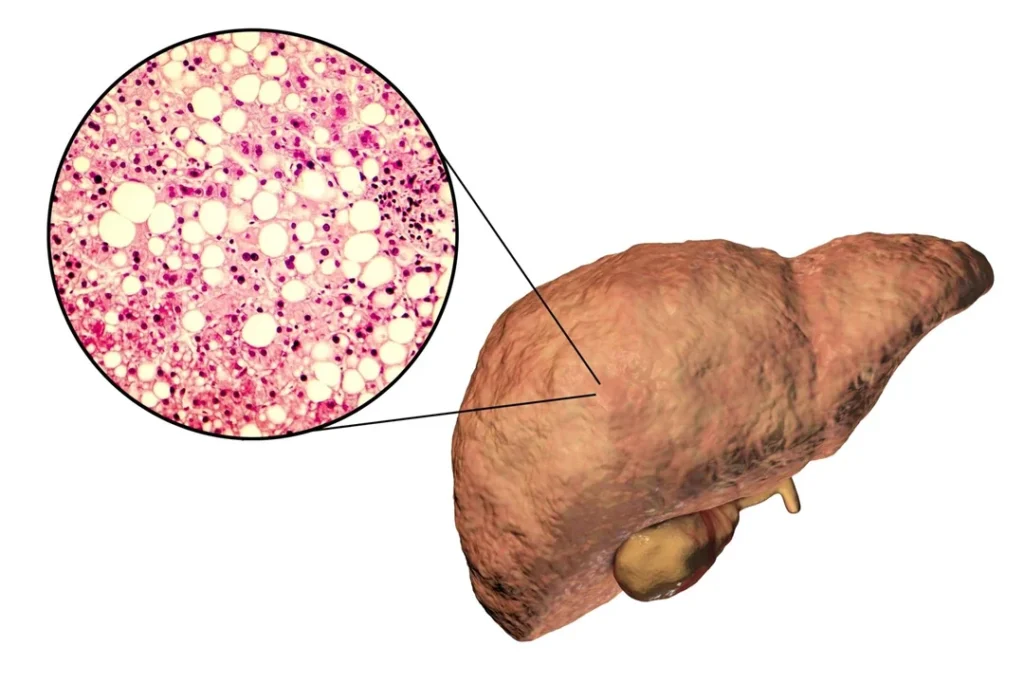

The problem is not just fat…

The problem is your liver has stored this fat for years… and it has become thickened and hardened

See it as oil in a pot for months. It turns into a thick, solid block

You can’t just rinse it out. It’s stuck

This is exactly what is happening inside your liver right now

This stored liver fat makes your liver stiff… suffocates its ability to produce energy… and reduces its functions